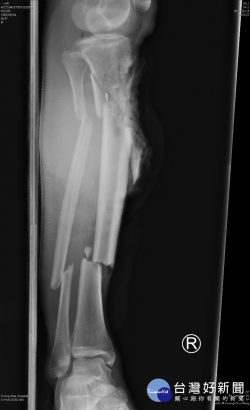

車禍腿斷6截血肉模糊恐截肢 彰醫重建整合終於撿回一隻腿

彰化縣54歲的王先生走在馬路上遭機車高速撞傷,右小腿光是大節的骨頭就斷了6截,小碎骨不計其數,碎肉都飛到不見了,骨頭外露血肉模糊,一般而言,為了怕危及生命,通常採截肢處理,經彰化醫院急診室的整形外科醫師呂明川判斷可以重建,與骨科醫師李文宏整合進行手術,終於讓王先生回復完整的右小腿。 醫師呂明川指出,王先生在3個月前被機車高速撞傷,當天到達急診室時右小腿嚴...... [閱讀更多]